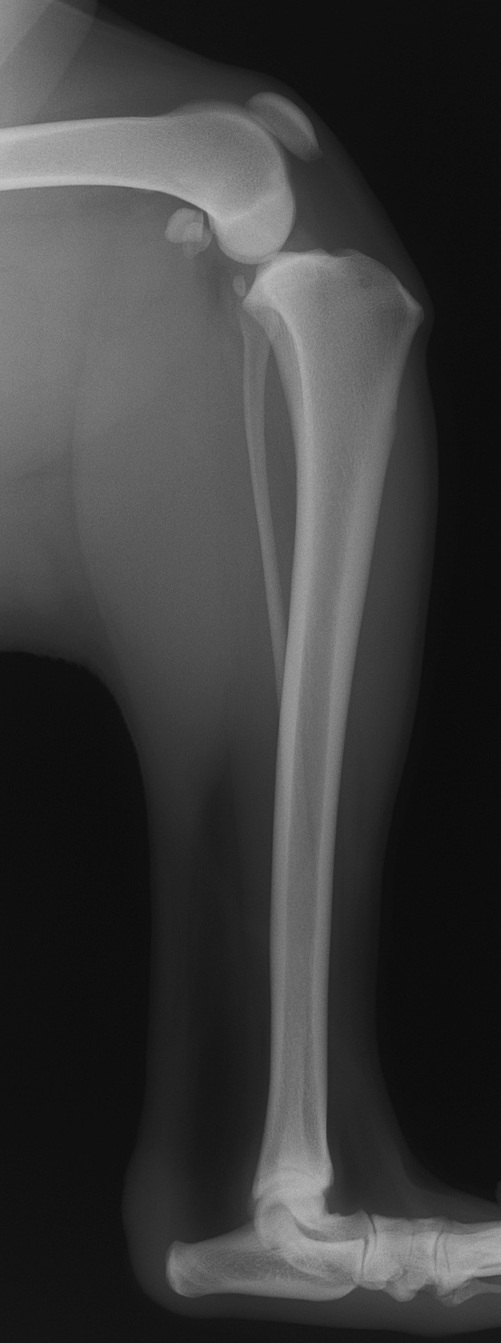

膝の安定性に重要な役割をしている前十字靭帯が断裂すると、下の写真のように大腿骨に対して脛骨の前方変位が起こります。カイちゃんは2年ほど前に右の前十字靭帯の断裂を起こしました。今回は、左の前十字靭帯を断裂しました。

正常な膝関節

前十字靭帯断裂時